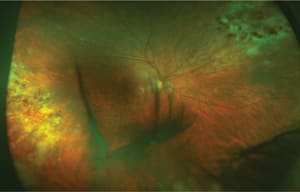

Of these diseases, retinitis (Figures 1-4) occurs at a greatly increased rate compared to other CMV diseases, at least in AIDS patients,2 and it confers an increased risk of mortality.3

Figure 1. CMV retinitis displaying frosted branch angiitis.

Retinal lesions commonly appear peripherally in a peri-vascular distribution as a creamy white infiltrate, with a more granular border comprised of smaller satellite lesions. Less obviously involved spaces of “clear” retina separate the granular foci.

However, with time, these areas progress to active retinitis and scarring, suggesting involvement with the virus from the beginning. The active border generally advances posteriorly, at a rate of 250-350 μm/week, leaving a swath of scarred and necrotic retina with mottled pigmentation of the RPE in its wake. Lesions presenting more posteriorly can involve the retinal vessels and cause retinal hemorrhages, giving rise to the term “pizza pie” retinitis.